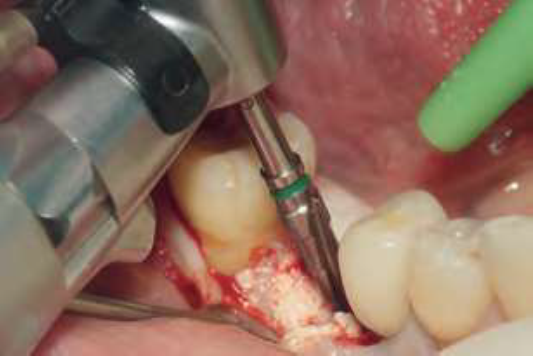

Após oito meses, o paciente realizou uma nova TCFC, sendo visualizado um ganho em volume na região do elemento 46 em comparação ao exame inicial (Figura 9). Seguiu-se então um segundo tempo cirúrgico. Após todos os passos de antissepsia e anestesia, foram realizados incisão em rebordo alveolar e descolamento para visualização do tecido neoformado. Em seguida, foi realizada a fresagem seguindo a sequência recomendada pelo fabricante para a inserção do implante dentário (4mm x 11mm, Maestro Hl Switch, Implacil De Bortoli), sendo iniciada com a fresa lança helicoidal subsequente das fresas cônicas com dimensões de 3,5mm x 11mm e 4mm x 11mm.

O implante foi inserido com o motor cirúrgico até a visualização do travamento em 46 Ncm, com a sua inserção final concluída através da catraca cirúrgica ao atingir o torque de inserção de 60 Ncm. Finalmente, o leito cirúrgico foi fechado com sutura utilizando fio de seda (Figuras 10 a 15). Após seis meses da inserção do implante, a reabertura cirúrgica foi realizada com a técnica de punção com broca cilíndrica diamantada, seguida pela colocação do cicatrizador (Figuras 16 e 17).